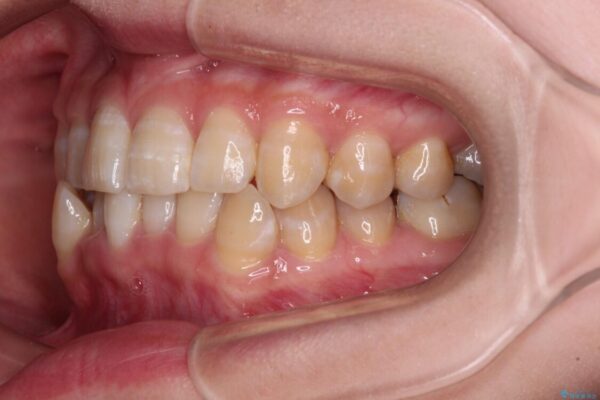

下顎の八重歯を気にして来院された患者様です。

下顎前歯にデコボコが集中していたため、顎間ゴムによる後方移動とIPR(歯と歯の間を削ること)により歯列を整えることとしました。

治療前、下顎前歯のデコボコが集中しており、奥歯の咬み合わせは、上顎に対して下顎が前方位にある状態でした。下顎の歯列を後方へ移動させる治療はインビザラインの得意とするところですので、1年程度で無事に治療を終えることができました。

• 【モニター】下顎前歯のデコボコをインビザラインできれいに 治療前画像